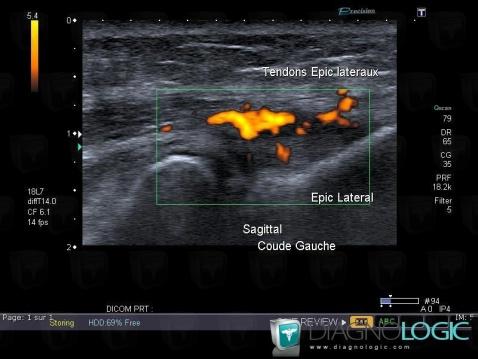

The images below illustrate this case for diagnoses Tendinopathy - enthesopathy Elbow / Epicondyle, for the modalities (US)

Tendinopathy - enthesopathy Elbow  / Epicondyle, Lateral epicondyle muscles, US

- Diagnosis Tendinopathy - enthesopathy Elbow / Epicondyle, Location(s) Lateral epicondyle muscles, with gamuts